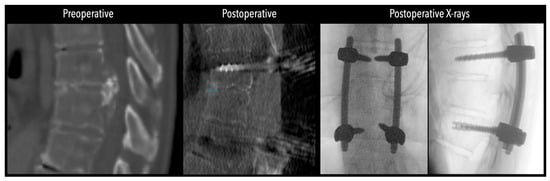

Figure 5. Left side: Comparative pre- and postoperative CT scan of a patient, illustrating complete discectomy. Right side: Postoperative X-rays illustrating fixation.

In three of the seven cases, the exiting nerve root at the level of the herniation was ligated due to poor visualization and transected extradurally to improve access. In the remaining four patients, the nerve root was either preserved or dissected intradurally using isocool bipolar diathermy and microsurgical scissors. With gentle medial retraction of the cord under gravity and protection using a micro-patty, the calcified disc was exposed. The ventral dura, when intact, was incised sharply and dissected from the disc surface where possible (Figure 2a,b and Figure 3). Disc removal was performed using a hockey-stick-shaped Misonix bone scalpel with constant irrigation, guided by intraoperative neuronavigation. The disc material was resected to a depth of 1–2 mm beyond the posterior vertebral wall to ensure adequate decompression. A second O-Arm spin was routinely performed following discectomy to confirm satisfactory decompression, especially given the limitations of the postoperative MRI due to the metal artefact (Figure 4, Figure 5 and Figure 6).